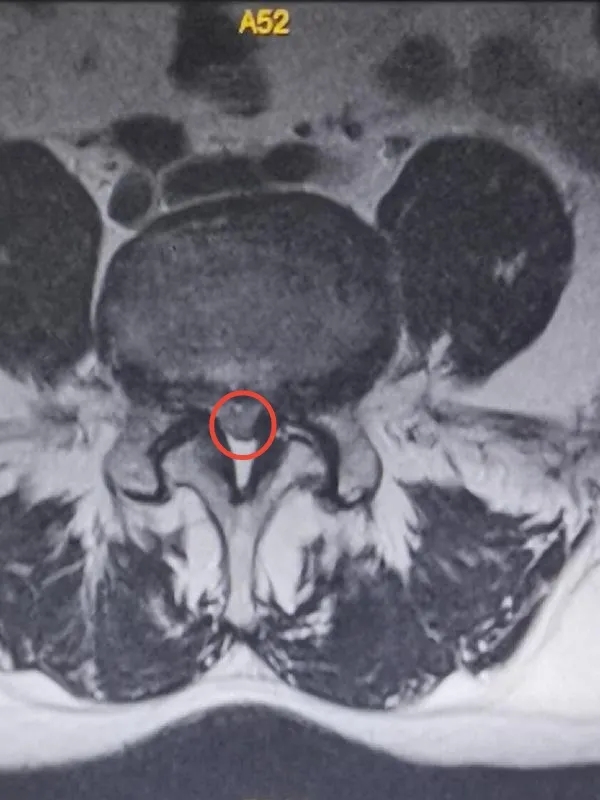

术前磁共振显示椎管狭窄,神经受压明显

经人介绍,王先生慕名来到附属医院脊柱、骨病外科就诊,医生通过仔细问诊、查体,完善相关检查后,确定王先生所患的是腰椎管狭窄症,“增厚的韧带和增生的骨质压迫了神经,不走路还表现不明显,一旦走远,神经的血运就跟不上来,就会感觉腿痛、腿麻。”医生告诉王先生。